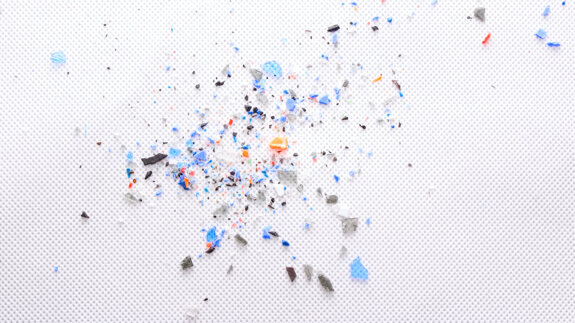

Ryc. 1-3_Stan przed leczeniem: 1. Zdjęcie wewnątrzustne